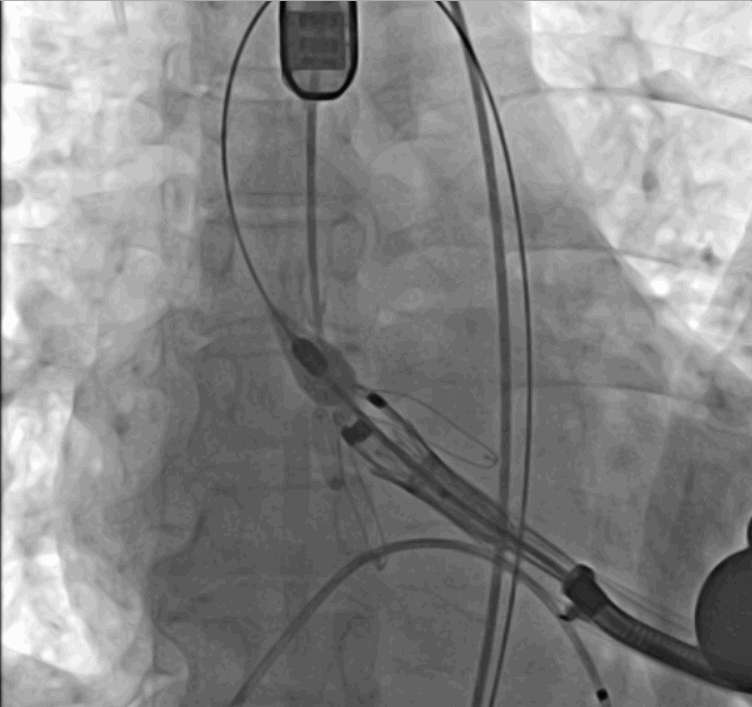

手術采用經心尖入路,對患者進行全麻后,在左側心尖處做3-4cm微創手術切口,在DSA及超聲引導下手術順利完成。從導入器械到完成瓣膜置入,僅耗時約10分鐘。術后即刻主動脈瓣返流程度由術前大量返流轉為消失,患者于導管室拔除氣管插管,次日由ICU轉入普通病房。

術中瓣膜釋放過程